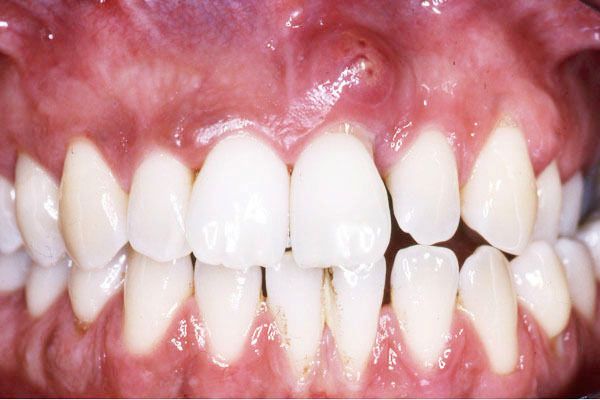

- Δεν είναι λίγες οι φορές, που ασθενείς με περιοδοντίτιδα (νόσος των ούλων και του οστού γύρω από το δόντι) εμφανίζουν ακρορριζικά αποστήματα (απόστημα στο άκρο της ρίζας του δοντιού), τα οποία θεραπεύονται με απονεύρωση . Στην προκειμένη περίπτωση τα μικρόβια που υπάρχουν στους περιοδοντικούς θυλάκους, είναι δυνατόν να περάσουν από την τρύπα που υπάρχει στο άκρο της ρίζας του δοντιού και να εισχωρήσουν στους ριζικούς σωλήνες (ρίζες του δοντιού). Αποτέλεσμα είναι η μόλυνση του πολφού (εσωτερικό του δοντιού), η οποία μπορεί να αντιμετωπιστεί μόνο με την ενδοδοντική θεραπεία.